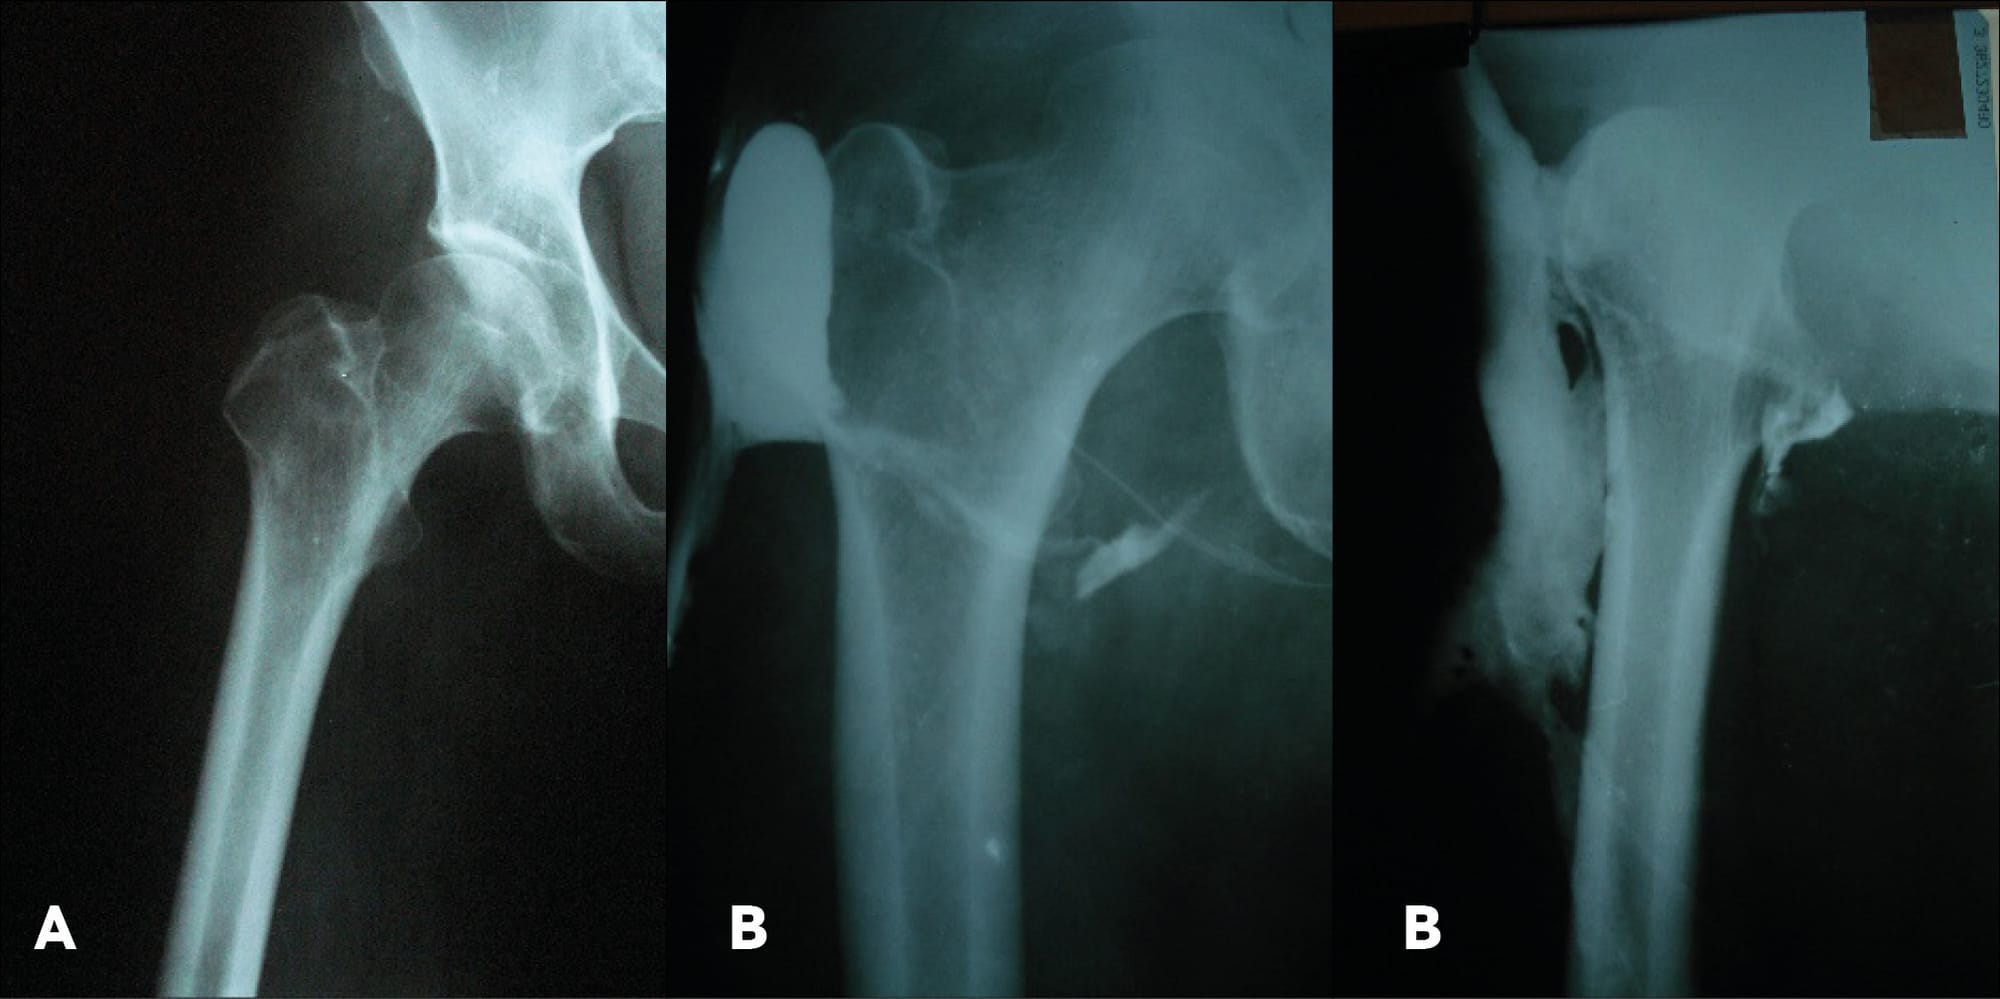

The patient was examined clinically and radiologically. Fistulography was performed (Figure 1).

The diagnosis was established as: chronic osteomyelitis of the lesser trochanter of the right femur. A surgery was performed — resection of the right femur’s lesser trochanter, necroectomy.